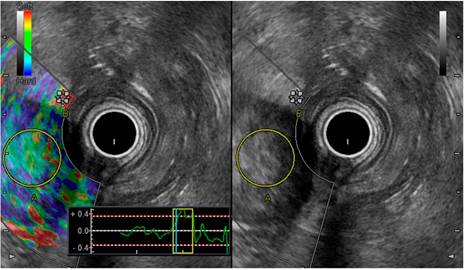

Ante el hallazgo de masa o adenomegalia retroperitoneal, las cuales no son presentaciones usuales de un tumor estromal tipo GIST, se realizó una ultrasonografía endoscópica 8 gástrica con el equipo radial Pentax-Noblux y en la visión endoscópica se identificó una lesión subepitelial en la curvatura mayor de la unión antrocorporal; en la visión ecográfica se trata de una lesión hiperecogénica de 40 x 38 mm de bordes bien definidos sin calcificaciones ni necrosis, que compromete toda la pared del estómago (Figura 3).

Posteriormente, se realizó una elastografía cualitativa 9 de color azul-verde y cuantitativa strain ratio de 10 y strain histograma del 95 %. En la ventana duodenal se identificó una adenopatía de 40 x 45 mm retropancreática hiperecogénica de bordes bien definidos (Figura 4). A continuación, se documentó una elastografía de color azul al realizar elastografía cualitativa, strain ratio de 10 y strain histograma del 44 % (Figura 5).